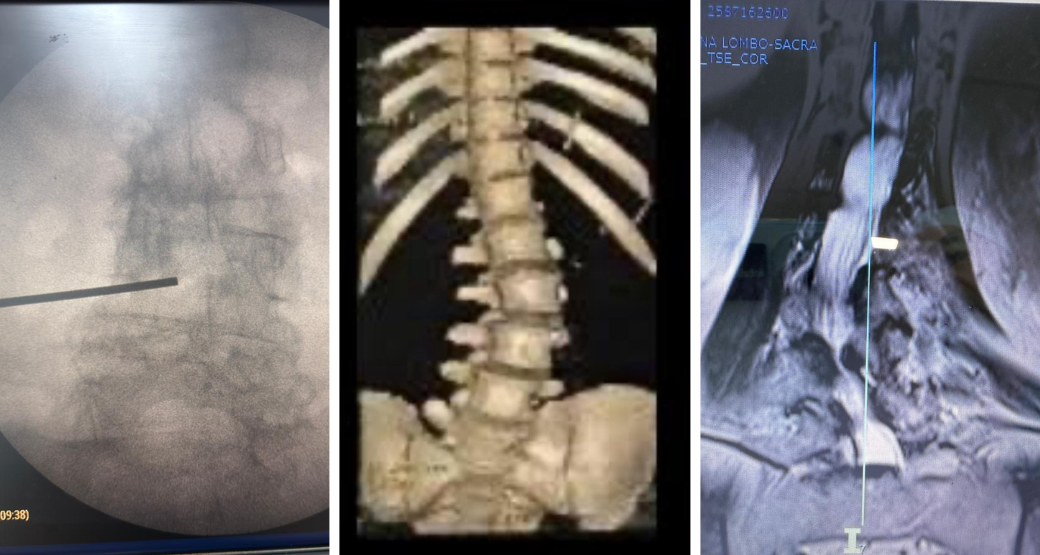

Descompressão endoscópica: Alívio para compressão radicular nas raízes L4 e L5?

“Sem dúvida... Realizamos com sucesso o procedimento em nosso paciente que sofria de dor lombar irradiada para membros inferiores e fraqueza muscular”, comemoram Edward Robert e Renato Bastos, cirurgiões ortopédicos.